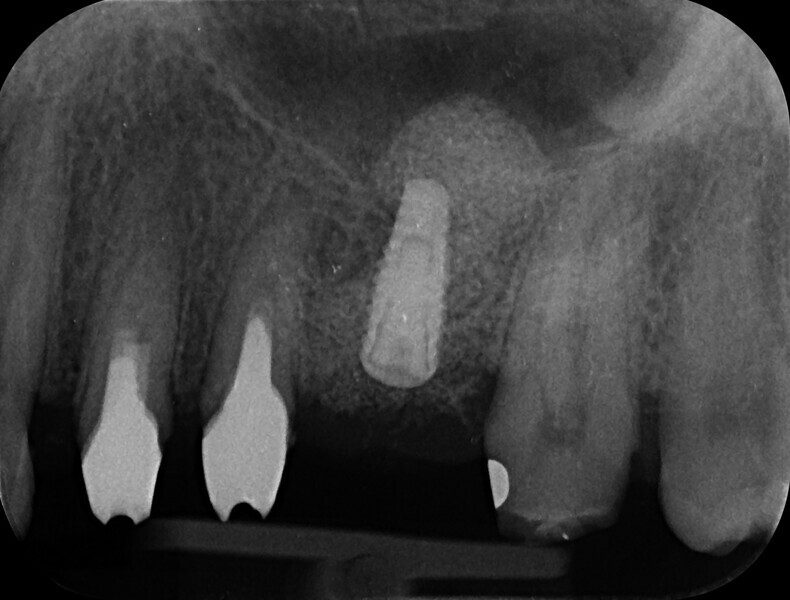

Minimally invasive root canal shaping—A new protocol